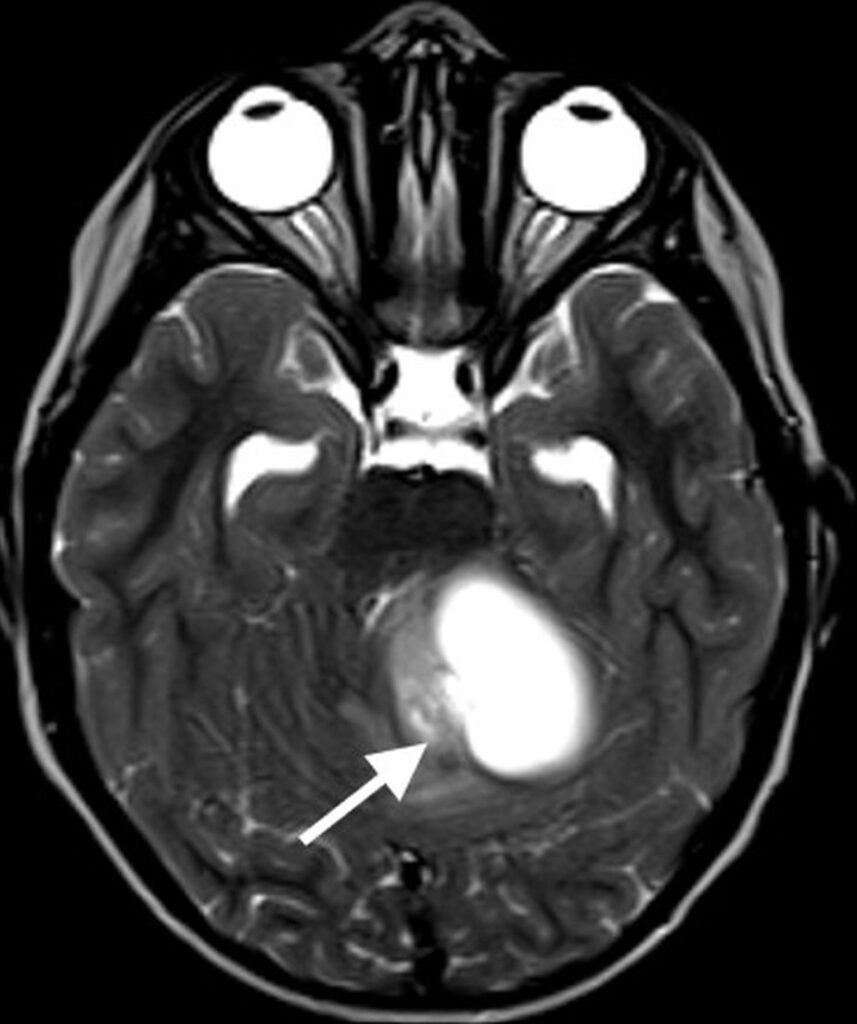

Ependymomas are the third most common primary posterior brain tumors, after medulloblastomas and pilocytic astrocytomas. The majority are classic, WHO grade 2, ependymomas, with more aggressive anaplastic ependymomas being WHO grade 3. Ependymomas are soft, pliable tumors that originate in or near the fourth ventricle and squeeze through the outlet foramina into adjacent spaces and cisterns. Because of their pliability, they often surround or encase neurovascular structures.

On MRI, ependymomas tend to be heterogeneously T2 hyperintense with variable enhancement. Cystic change and calcifications are common, with calcifications occurring in up to 50% of cases, much more common than is seen with medulloblastomas [7]. Given the relative pliability of the tumor, extension through fourth ventricular outlet foramina is characteristic. The presence of reduced or restricted diffusion is variable, but typically less than is seen with highly cellular medulloblastomas. The exception is with anaplastic ependymomas, which may have areas of restricted diffusion that are similar to medulloblastomas. Anaplastic ependymomas tend to have a higher frequency of disseminated metastatic disease and disease recurrence, with a poorer prognosis compared to lower-grade ependymomas [22]. The frequency of disseminated metastatic disease for ependymomas is less than that for medulloblastomas.